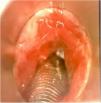

Paciente de 49 años (IMC 29,4 kg/m2 y ASA III) con estenosis subglótica (ES) de más de 70% (grado III) intervenida mediante resección láser y posterior dilatación. Durante la resección láser se empleó ventilación controlada por flujo utilizando el respirador Evone®, que permite controlar todo el ciclo respiratorio regulando tanto el flujo inspiratorio como el espiratorio sin comprometer el intercambio gaseoso a pesar de administrar FIO2 máxima de 0,3 por riesgo de ignición. Antes de proceder a la dilatación endoscópica, se retiró el tubo endotraqueal láser de 4,5 mm de diámetro interno y se inició terapia con gafas nasales de alto flujo (GNAF) para prolongar la oxigenación apneica. El tiempo total de apnea fue de 11 minutos, manteniendo en todo momento SpO2 > 98% y End Tidal de CO2 máximo de 60 mmHg.

A 49-year old patient (BMI 29.4 kg/m2 and ASA III) with grade III subglottic stenosis (> ventilator in flow controlled ventilation mode, which allowed us to regulate both inspiratory and expiratory flow without compromising gas exchange despite maintaining peak FIO2 at 0.3 due to the risk of ignition. Before proceeding with endoscopic dilation, the 4.5 mm laser endotracheal tube was withdrawn and high flow nasal cannula oxygenation was started in order to prolong apnoeic oxygenation. Total apnoea time was 11 minutes, maintaining SpO2 > 70%) underwent laser resection followed by dilation. During resection he was ventilated by the Evone > ventilator; high flow nasal cannula therapy; apnoeic oxygenation-98% and peak EtCO2 60 mmHg throughout the procedure.